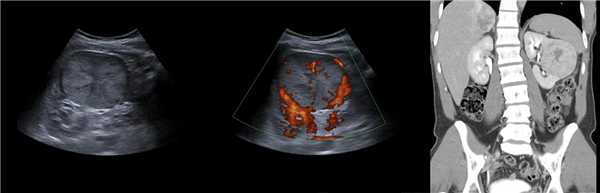

Рисунок. Двустороннее уретероцеле на УЗИ: в режиме ЦДК из верхушек уретероцеле определяется выброс мочи.

На УЗИ в мочевом пузыре или в уретре определяется анэхогенное образование, округлой формы, с четким и ровным контуром; соответствующий мочеточник обычно заметно расширен; может присутствовать гидронефроз верхней части удвоенной почки. Уретероцеле определяют как внутрипузырные (полностью внутри мочевого пузыря) или внепузырные (некоторая часть постоянно расположена в шейке мочевого пузыря или в уретре).